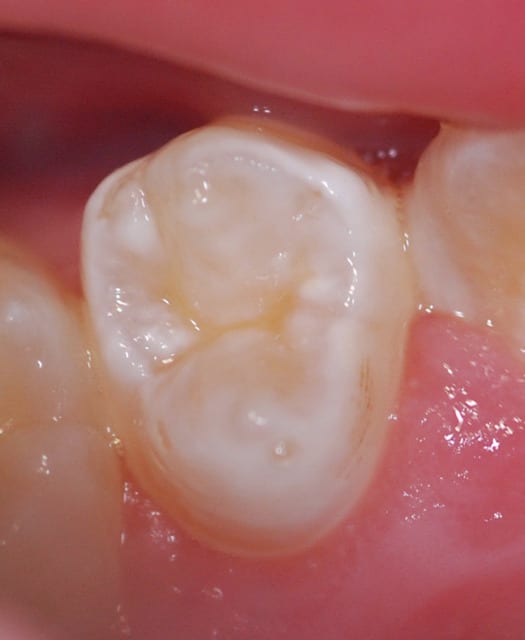

Et voilà mes débuts.

D'abord un cas.... sympa. Première étape, bridge 3 dents antérieur, le patient a un partiel résine qui lui prend les 3/4 du palais pour une bête dent....

Puis un exemple type de mes petits plaisirs : replacer mes provisoires sur les MPU. l'espace, c'est à cause de 2 raisons : UN c'est une provisoire à tenon intégré, 2 je n'ai pas bien nettoyé le ciment de scellement. Mais c'est déjà pas mal, des fois je vois les provisoires des confrères, surcontour d'1mm, mal détourée, moralité gencive inflammée et toute "dégueu"....

Pour la première, la profondeur de champs est pas "top", mais c'est moi qui ai merdé.

Le point AF est sur les centrales.

J'ai rectifié le tir sur les suivants en sélectionnant un point AF latéal, et en faisant le cas échéant une MAP manuelle sur le côté.

Sinon j'ai une question : est-ce qu'avec un flash annulaire en vraie macro, vous avez le même reflet du flash que sur mon cliché des centrales ?

A noter que ce qui joue surement, c'est que je n'ai pas séché les dents, ni la gencive.

Peut-être étais-je trop près ? j'avais mis l'objectif en MAP manuelle, sélectionné le rapport 1:1 qui est obtenu à 28,6cm du sujet....

Ou si c'est le flash qui est trop "intense" au niveau de la LED, pas assez "étouffé" ? (bon un flash à 80€ hein......)

Merci de vos avis !